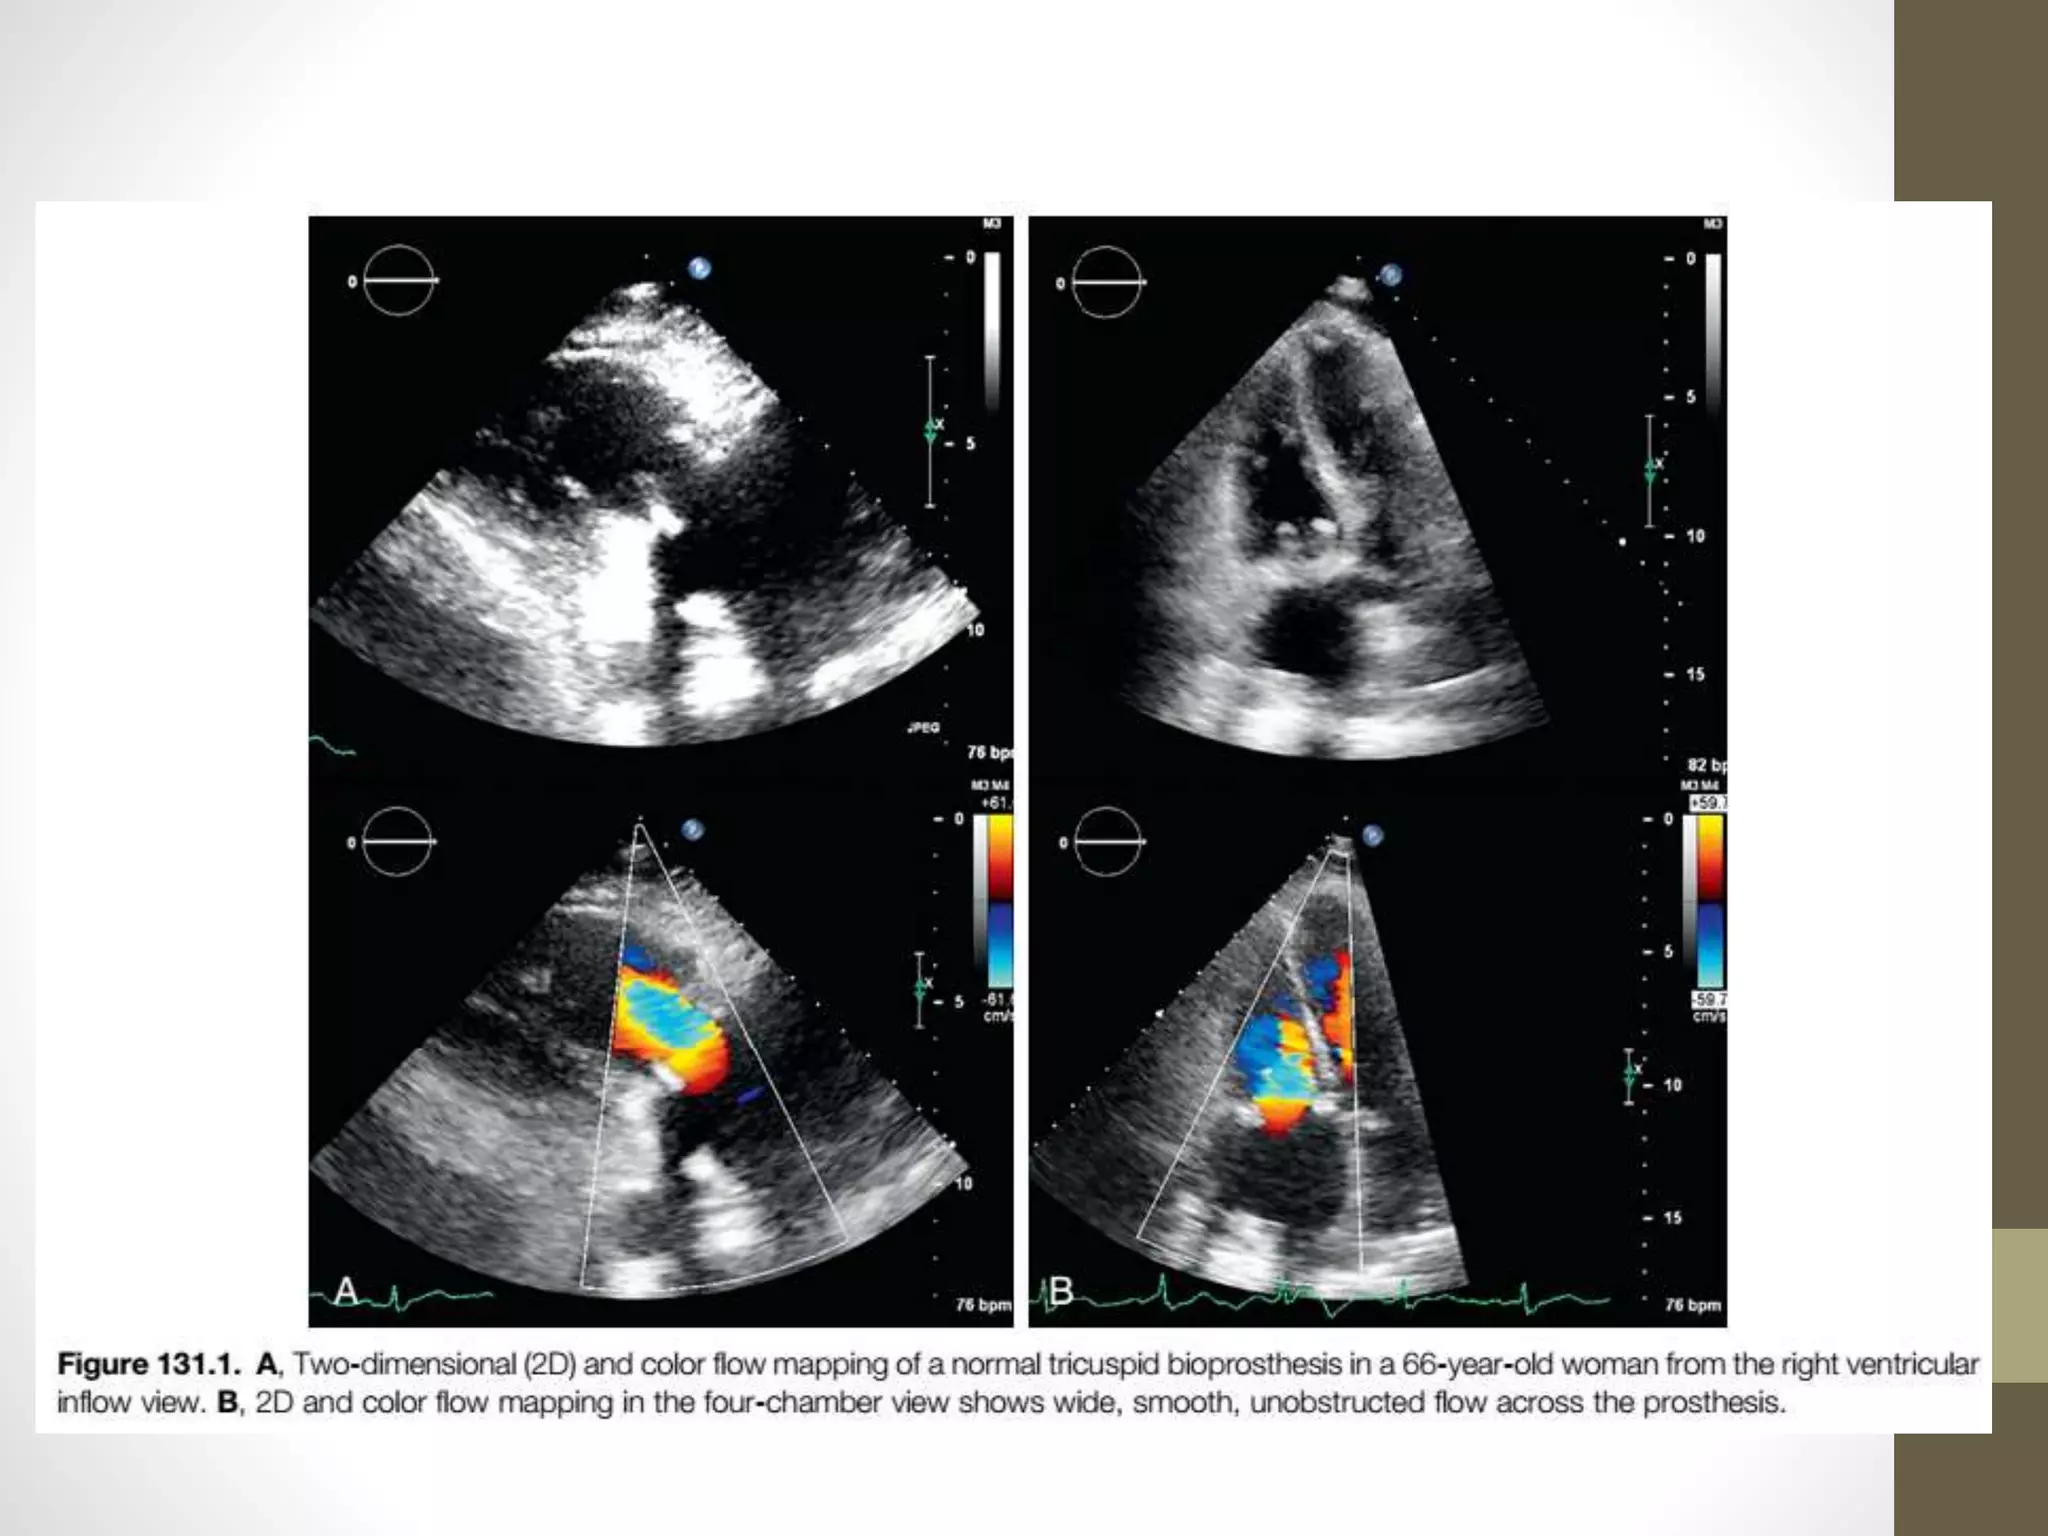

• Patients with normally functioning valves have a normal

physical examination, and the prosthesis appears to have

normal motion and flow pattern by TTE and TEE.

• Current guidelines recommend the early evaluation of

tricuspid prosthesis post implantation.

• It is important to average Doppler measurements from at

least five cardiac cycles

• because measurements may vary significantly because of

respiration in the tricuspid position.